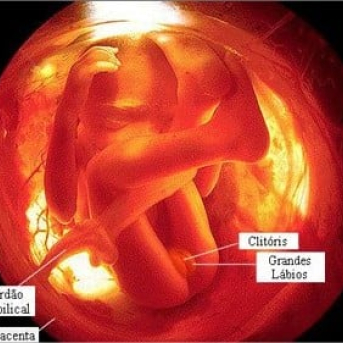

Já na 19ª semana da gravidez, o sistema sensorial do feto está em plena evolução. Uma substância chamada mielina2 começa a se formar na região dos neurônios, ativando as sensações como ouvir sons, sentir cheiros, saborear sabores e sentir toque. É uma fase muito importante, que fará o sistema nervoso funcionar devidamente. Se ainda não sabe o sexo, agora irá conseguir. Afinal, os órgãos genitais já estão completamente desenvolvidos, ficando totalmente visíveis.